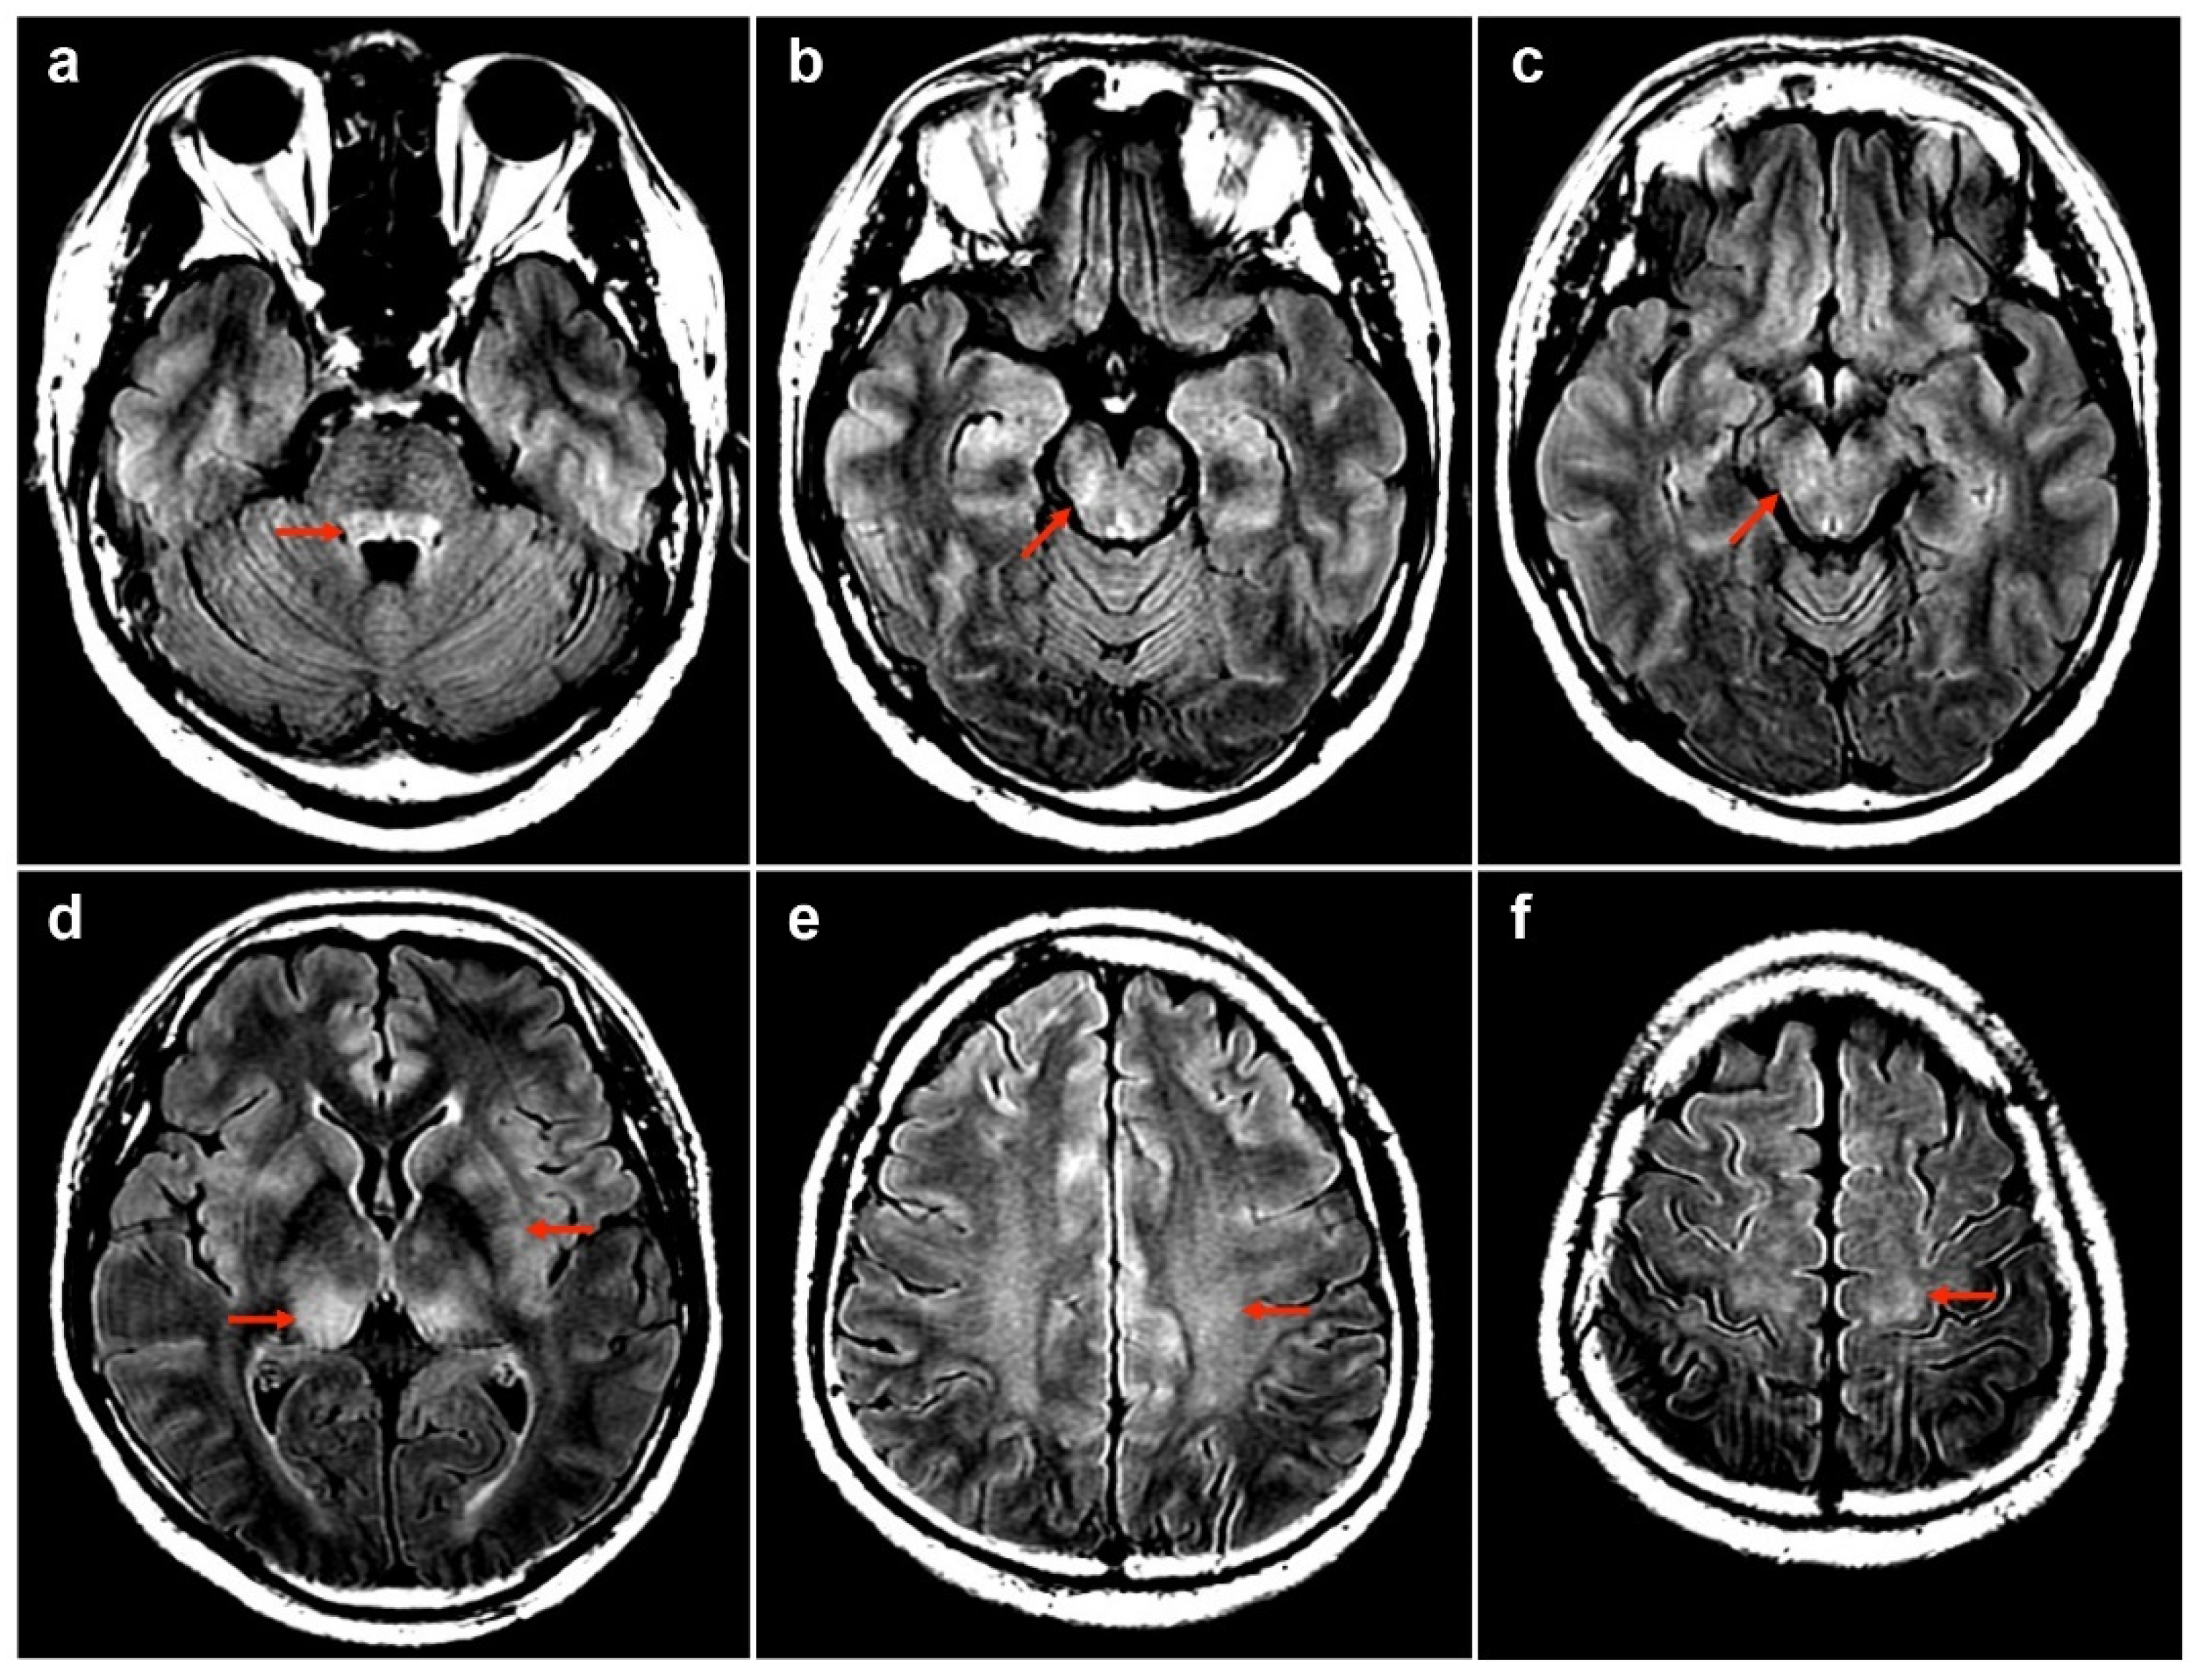

| 1 | 50M/HBV carrier | 1st AZ/13 | MOGAD | - | + | - | 175 | 99 | 0 | 78.1 | 0.47 | NA | Bil thalami, pu, subcortical WM, brainstem | T3-T4 | PT | R | Index case |